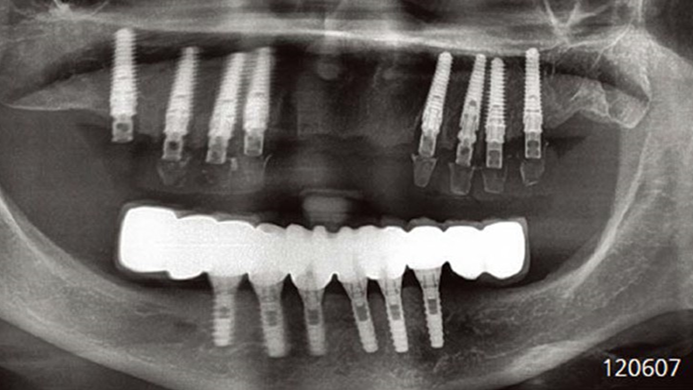

Clinical case: Advantage of fuse abutment with AnyRidge implant for immediate loading in

upper fully edentulous case

- Courtesy of Dr. Kwang Bum Park -

“AnyRidge shows excellent esthetic results

with Zirconia prosthesis in full-mouth rehabilitation case . ”

“AnyRidge shows excellent initial stability

& stable results after immediate loading in

upper fully edentulous case. ”